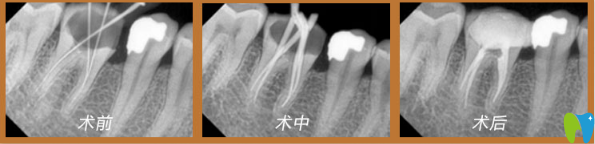

董克文院長(zhǎng)真人案例:

謝先生,33歲,癥狀:牙齒蛀蟲(chóng);解決方案:歐式無(wú)痛顯微根管治療。

術(shù)前口述:患上牙髓炎十分痛苦,特別是夜里,劇烈疼痛,吃止疼藥根本不管用,平日吃東西也不敢嚼,人都憔悴了。

術(shù)后感言:治療的時(shí)候醫(yī)生首先在牙齒上鉆一個(gè)洞(打過(guò)麻藥的情況),將炎性分泌物釋放出來(lái),效果立竿見(jiàn)影,馬上就感覺(jué)牙齒不疼了。牙疼是病,得治!